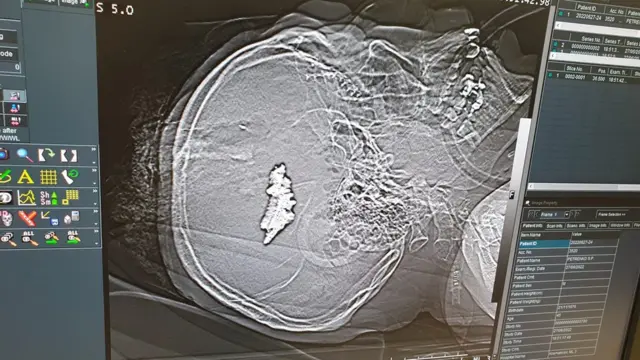

У нього була черепно-мозкова травма - ця лікарня спеціалізується на таких пораненнях.

"У нас був хлопець 2002 року народження, з такою черепно-мозковою травмою, що на ньому відразу поставили хрест - там декілька осколків, один із них біля мосту, це дуже віддалена частина мозку, і навіть якщо нейрохірург його фізично витягне, найбільша вірогідність того, що людина залишиться в комі, овочем до кінця своїх днів", - розповідає Валерія.